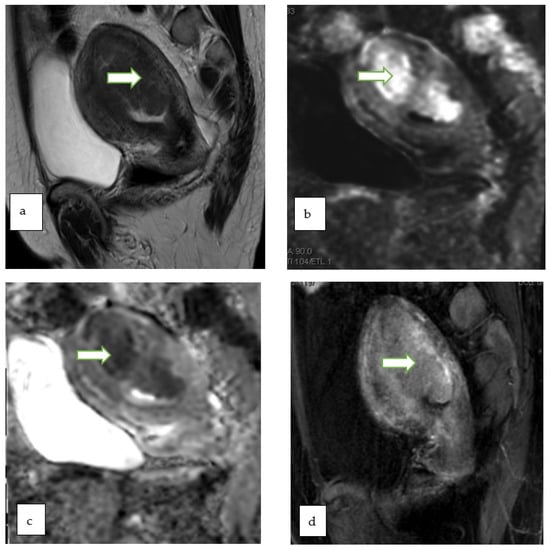

| 4 | Intermediate risk | ~50% | Lesion with solid tissue (excluding T2 dark/DWI dark) - Intermediate risk time intensity curve on DCE MRI - If DCE MRI is not feasible, score 4 is any lesion with solid tissue (excluding T2 dark/DWI dark) that is enhancing ≤ myometrium at 30–40 s on non-DCE MRI |

| Lesion with lipid content - Large volume enhancing solid tissue | |||

| 5 | High risk | ~90% | Lesion with solid tissue (excluding T2 dark/DWI dark) - High risk time intensity curve on DCE MRI - If DCE MRI is not feasible, score 5 is any lesion with solid tissue (excluding T2 dark/DWI dark) that is enhancing > myometrium at 30–40 s on non-DCE MRI |

| Peritoneal, mesenteric or omental nodularity or irregular thickening with or without ascites |